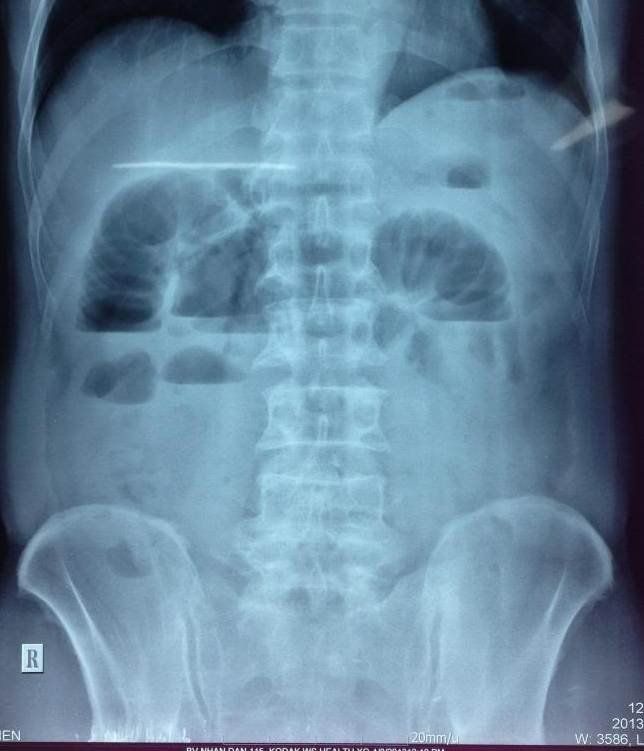

Chụp X-quang là một xét nghiệm ban đầu được thực hiện để chẩn đoán tắc ruột. Các phát hiện trên phim chụp X-quang gợi ý tắc ruột bao gồm các quai ruột giãn với mức khí – dịch, ruột xẹp ở đoạn xa, không có khí trong bụng hoặc có cách khác là dấu hiệu "chuỗi ngọc" cho thấy đầy hơi bị kẹt trong thành ruột.

Phương tiện hình ảnh học với x quang bụng chỉ có độ nhạy 50-60% đối với tắc ruột non. Trong hầu hết các trường hợp, X quang bụng sẽ có các đặc điểm gợi ý khả năng tắc ruột non như sau:

- Các quai ruột non giãn ra gần đến chỗ tắc nghẽn

- Các vòng quai ruột giãn nở tập trung ở vùng trung tâm

- Đường kính của quai ruột giãn từ trên 2,5 - 3 cm là đạt yếu tố cần thiết hướng tới chẩn đoán tắc ruột

- Quan sát thấy các nếp vòng ở ruột non, chạy vòng quanh chu vi ruột

- Có mực nước hơi nằm ở vùng trung tâm

- Trong cùng một vòng ruột nhưng mực nước hơi ở các độ cao khác nhau (chiều cao chênh lệch từ trên 2 cm).

Bụng chướng đầy hơi. Tuy nhiên, nếu phim chụp x quang tắc ruột non không thấy dấu hiệu này thì cũng không thể loại trừ được chẩn đoán. Nguyên nhân là vì trong tắc ruột non là tắc ruột cao, bụng có thể ít khả năng bị chướng khí hơn so với tắc ruột thấp như tắc đại tràng, do khí thoát ra ngoài qua phản xạ nôn ói của người bệnh hay đã được giải áp khi đặt ống thông dạ dày.

Dấu hiệu “chuỗi ngọc”: các túi khí nhỏ trong thành ruột khi trong lòng ruột non chứa đầy chất dịch